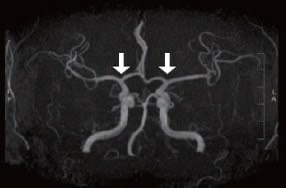

모야모야병은 뇌혈관, 특히 뇌로 혈액을 공급하는 내경동맥과 그 주변 주요 혈관이 점점 좁아지고 막히는 희귀 난치성 질환으로, 혈류가 줄어든 뇌는 부족한 혈액을 보충하기 위해 가느다란 미세측부혈관들을 새로 만들어냅니다. 이 작은 혈관들이 연기처럼 보인다고 하여 일본어로 ‘모야모야(안개·연기)’라는 이름이 붙었습니다. 소아부터 성인까지 폭넓게 나타나며, 특히 5~10세 어린이와 30대 전후의 여성에서 비교적 많이 발견되는 경향이 있습니다. 증상은 일시적 마비, 언어장애, 두통, 실신, 경련 등 매우 다양해 뇌졸중과 유사하거나 초기에는 가벼운 신경학적 증상으로만 나타나 진단이 늦어지기도 했습니다. 질환이 진행하면 허혈성 뇌졸중(뇌경색)이나 출혈성 뇌졸중 위험이 증가하여 반드시 전문적인 관리가 필요합니다. 아직 완전히 예방할 수 있는 방법은 없지만 조기 진단과 적절한 치료를 통해 뇌 기능을 보호하고 삶의 질을 유지할 수 있습니다.

모야모야병은 뇌기저부의 주요 혈관이 서서히 협착되고 막히면서 뇌혈류가 감소하는 만성 진행성 뇌혈관 질환입니다. 협착이 진행된 부위를 대신해 뇌는 생존을 위해 얇고 약한 혈관망을 만들어 혈류를 보충하려 하고, 이 새로운 혈관들이 촬영 영상에서 연기처럼 퍼져 보인다고 하여 ‘모야모야’라는 이름이 붙었습니다. 기전적으로는 내경동맥 말단부와 중대뇌동맥·전대뇌동맥의 기시부에 병변이 가장 잘 생기며, 시간이 지남에 따라 양쪽에 대칭적으로 나타나는 특징을 보였습니다. 이 질환은 단순한 혈관 협착이 아니라 진행성 변화이기 때문에 치료하지 않으면 혈류 부족이 심해지고 뇌 손상이 누적될 수 있습니다. 또한 뇌기능이 체력·호흡·체온 변화 등에 민감하게 반응하기 때문에 과호흡, 울음, 격렬한 운동, 감염 등으로 증상이 악화될 수 있습니다. 즉, 모야모야병은 시간이 지나면서 뇌혈류를 감소시키고 뇌졸중 위험을 높이는 질환이며, 평생 관리가 필요한 만성적 특성을 갖고 있습니다.

따라서 가족력이 있거나 의심되는 증상이 있다면 뇌 MRA·MRI 등의 정기검진이 도움이 되며, 조기 진단 시 치료 효과도 훨씬 높아집니다.